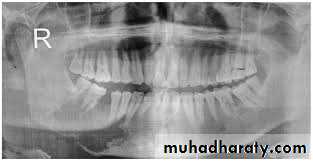

Radiographical appearance ;

It is possible to see a patient with acute osteomyelitis that has a normal-appearing orthopantomogram. However, one can often see the appearance of "moth-eaten" bone or sequestrum of bone, which is the classic appearance of osteomyelitis.14

Computerized tomography (CT) scans have become the standard in evaluating maxillofacial pathology such as osteomyelitis. its sensitive in late stage when 30%-50% of the bone demineralized.